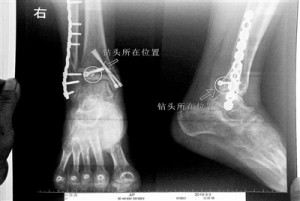

15、北京:女子做完手术钻头被落骨头里 院方称危害不大

看着X光片中自己腿内的异物,胡女士就感到莫名的担忧。胡女士于2013年3月在北京市丰台区右安门医院进行了一次骨折手术,术后医生才发现手术时用来打眼用的钻头不慎遗留在了胡女士的骨头中,并且无法取出。